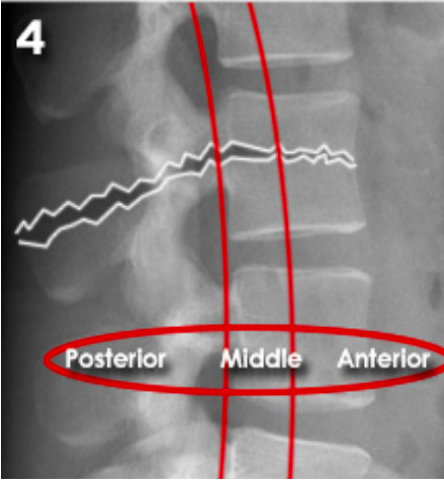

Lumbar three column model

Divides the spine into three columns: anterior, middle, and posterior

Used to determine the stability of thoraco-lumbar spine fractures

severity depends on how many columns are implicated

If spinal instability is suspected further imaging with CT or MRI should be considered

ANTERIOR (Stable):

Anterior compression injury

e.g. compression fractures (most common)

between the anterior longitudinal ligament to the middle of the vertebral body

MIDDLE (unstable):

'Burst' fracture (vertebral body crushed in all directions) due to axial loading

between middle of vertebral body to posterior longitudinal ligament

POSTERIOR (unstable):

Flexion-distraction fracture (caused by severe compression or rotation)

between posterior longitudinal ligament to spinous process

spinal cord implicated